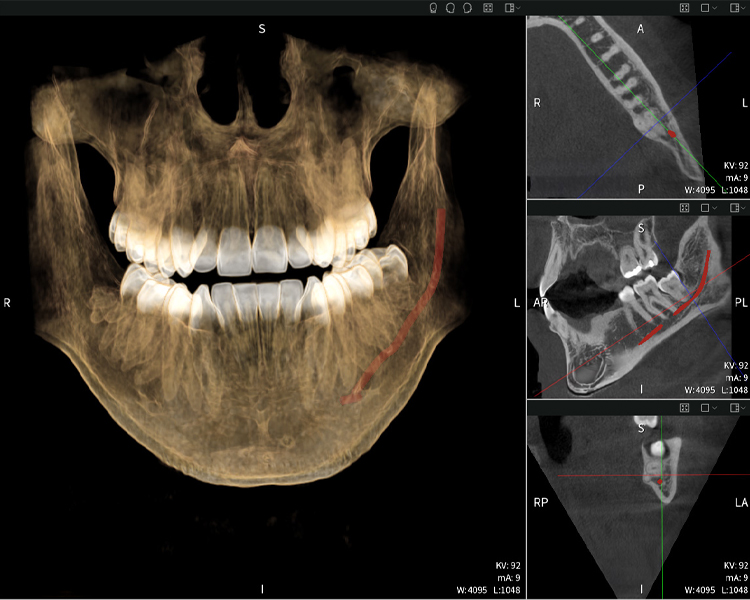

A continuación encontrarás un caso del Dr. med. dent. Oliver A. Centrella, en el cual las imágenes CBCT obtenidas con Seethrough Max proporcionaron información crucial sobre la anatomía compleja y la relación crítica entre las muelas del juicio y el nervio alveolar inferior. En este caso, existe una indicación para la extracción quirúrgica de las muelas del juicio.

Figura b: Resultados de imagen de Seethrough Max, sobre un fondo negro.

Figura b

Las figuras b–d muestran varias vistas de una reconstrucción 3D de la mandíbula, proporcionando una visión general completa de la anatomía mandibular, la posición de los nervios en relación con los dientes y permitiendo evaluar la simetría y alineación dentaria.

• Arriba a la izquierda: Corte axial de la mandíbula izquierda (región 38) que muestra el nervio alveolar inferior (en rojo) en proximidad a las raíces del diente 38.

• Arriba a la derecha: Reconstrucción 3D de toda la mandíbula para orientación. El nervio alveolar inferior marcado en rojo ilustra su ubicación dentro del hueso mandibular.

• Abajo a la izquierda: Vista sagital de la mandíbula (región 38), destacando la estrecha relación espacial entre las raíces y el conducto del nervio.

• Abajo a la derecha: Vista coronal de la mandíbula (región 38), crucial para evaluar la posición espacial de las raíces en relación con el nervio.